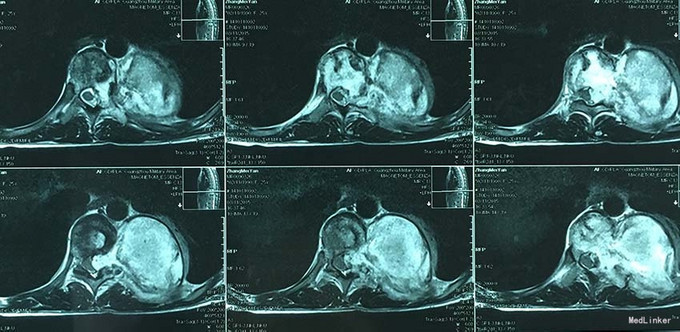

查体:脊柱外观无明显畸形,颈椎活动度正常,胸背部可见纵向长约15cm切口,皮肤钉缝合,伤口愈合可,无红肿渗液。胸椎9-10体左侧棘突旁局部压痛(+)、叩击痛(-),压头试验阴性,双侧侧臂丛牵拉实验(-),双上肢肌张力、运动、感觉及反射无明显异常、躯体感觉无明显减退,双下肢髂腰肌、股四头肌、胫前肌肌力IV级,感觉正常,双下肢直腿抬高试验(-),双侧腱反射对称略活跃,双侧Hoffman征(-),双侧Babinski征(-),双侧髌阵挛(-),踝阵挛(-)。 辅助检查:2015-11外院胸椎MRI检查发现T9-10节段椎体肿瘤并椎旁软组织肿块形成,肿块突入胸腔占位

诊断:胸椎椎体肿瘤(T9-10) 治疗:先于外院行1期后路椎弓根钉固定融合手术,然后转入我院行介入下术前椎体节段血管栓塞手术,第二天行经左侧胸腔入路椎体肿瘤病灶刮除并钛网植骨植入重建手术。术后恢复满意。复查MRI显示肿瘤病灶基本完全切除。